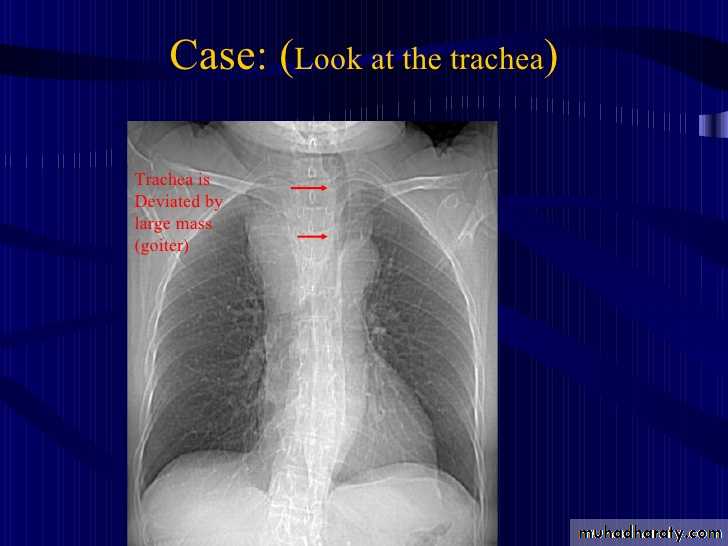

Retrosternal Goiter

25.retrosternal Goiter

26.retrosternal Goiter